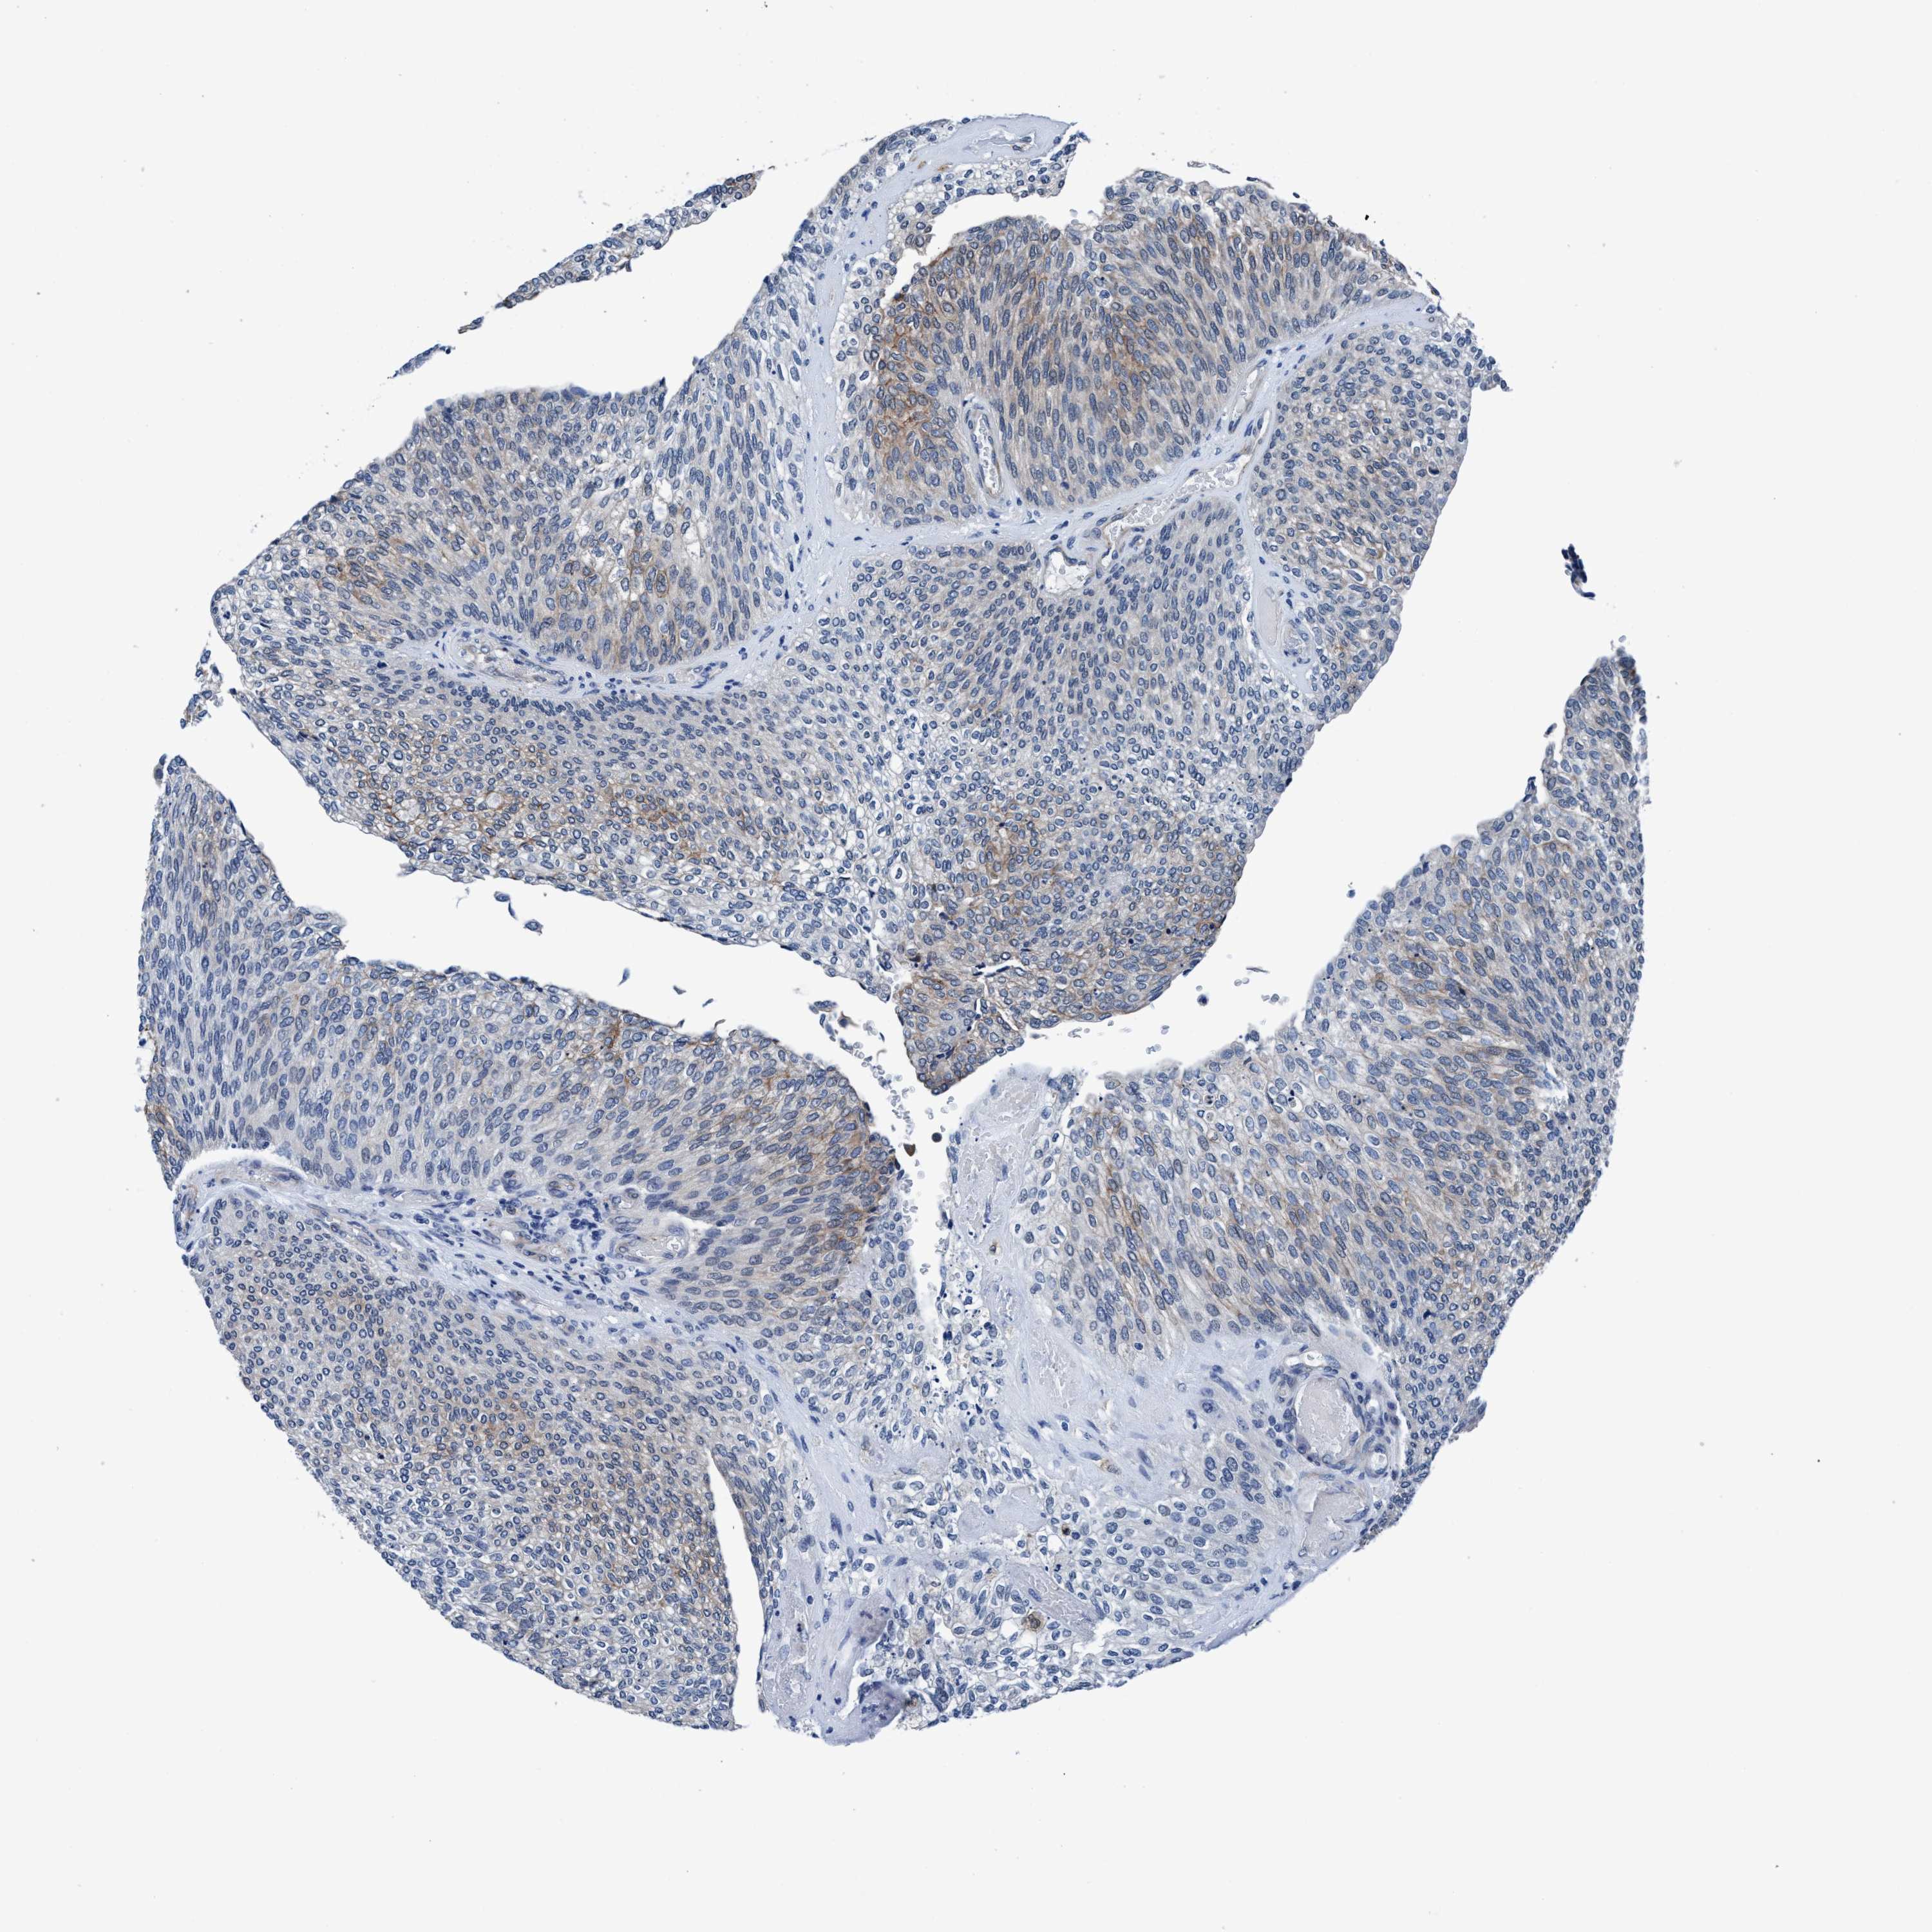

UROTHELIAL CANCER - Protein expressioni

A mouse-over function shows sample information and annotation data. Click on an image to view it in a full screen mode. Samples can be filtered based on level of antibody staining by selecting one or several of the following categories: high, medium, low and not detected. The assay and annotation is described here.

Note that samples used for immunohistochemistry by the Human Protein Atlas do not correspond to samples in the TCGA dataset.

Antibody stainingi

Antibody staining in the annotated cell types in the current human tissue is reported as not detected, low, medium, or high, based on conventional immunohistochemistry profiling in selected tissues. This score is based on the combination of the staining intensity and fraction of stained cells.

Each image is clickable and will lead to virtual microscopy that enables deeper exploration of all samples and also displays staining intensity scores, fraction scores and subcellular localization as well as patient and tissue information for each sample.

Antibody HPA008423

Staining

High

Medium

Low

Not detected

Intensity

Strong

Moderate

Weak

Negative

Quantity

>75%

75%-25%

<25%

None

Location

Urothelial carcinoma, Low grade

Urothelial carcinoma, High grade